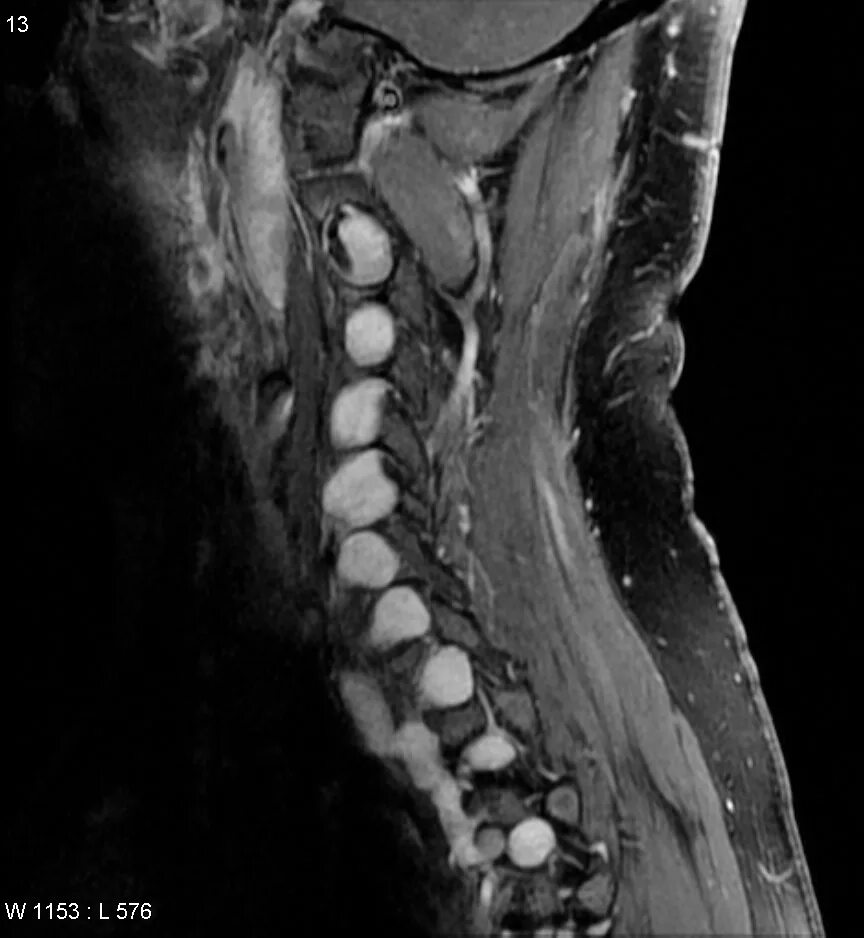

Нейрофиброматоз мрт